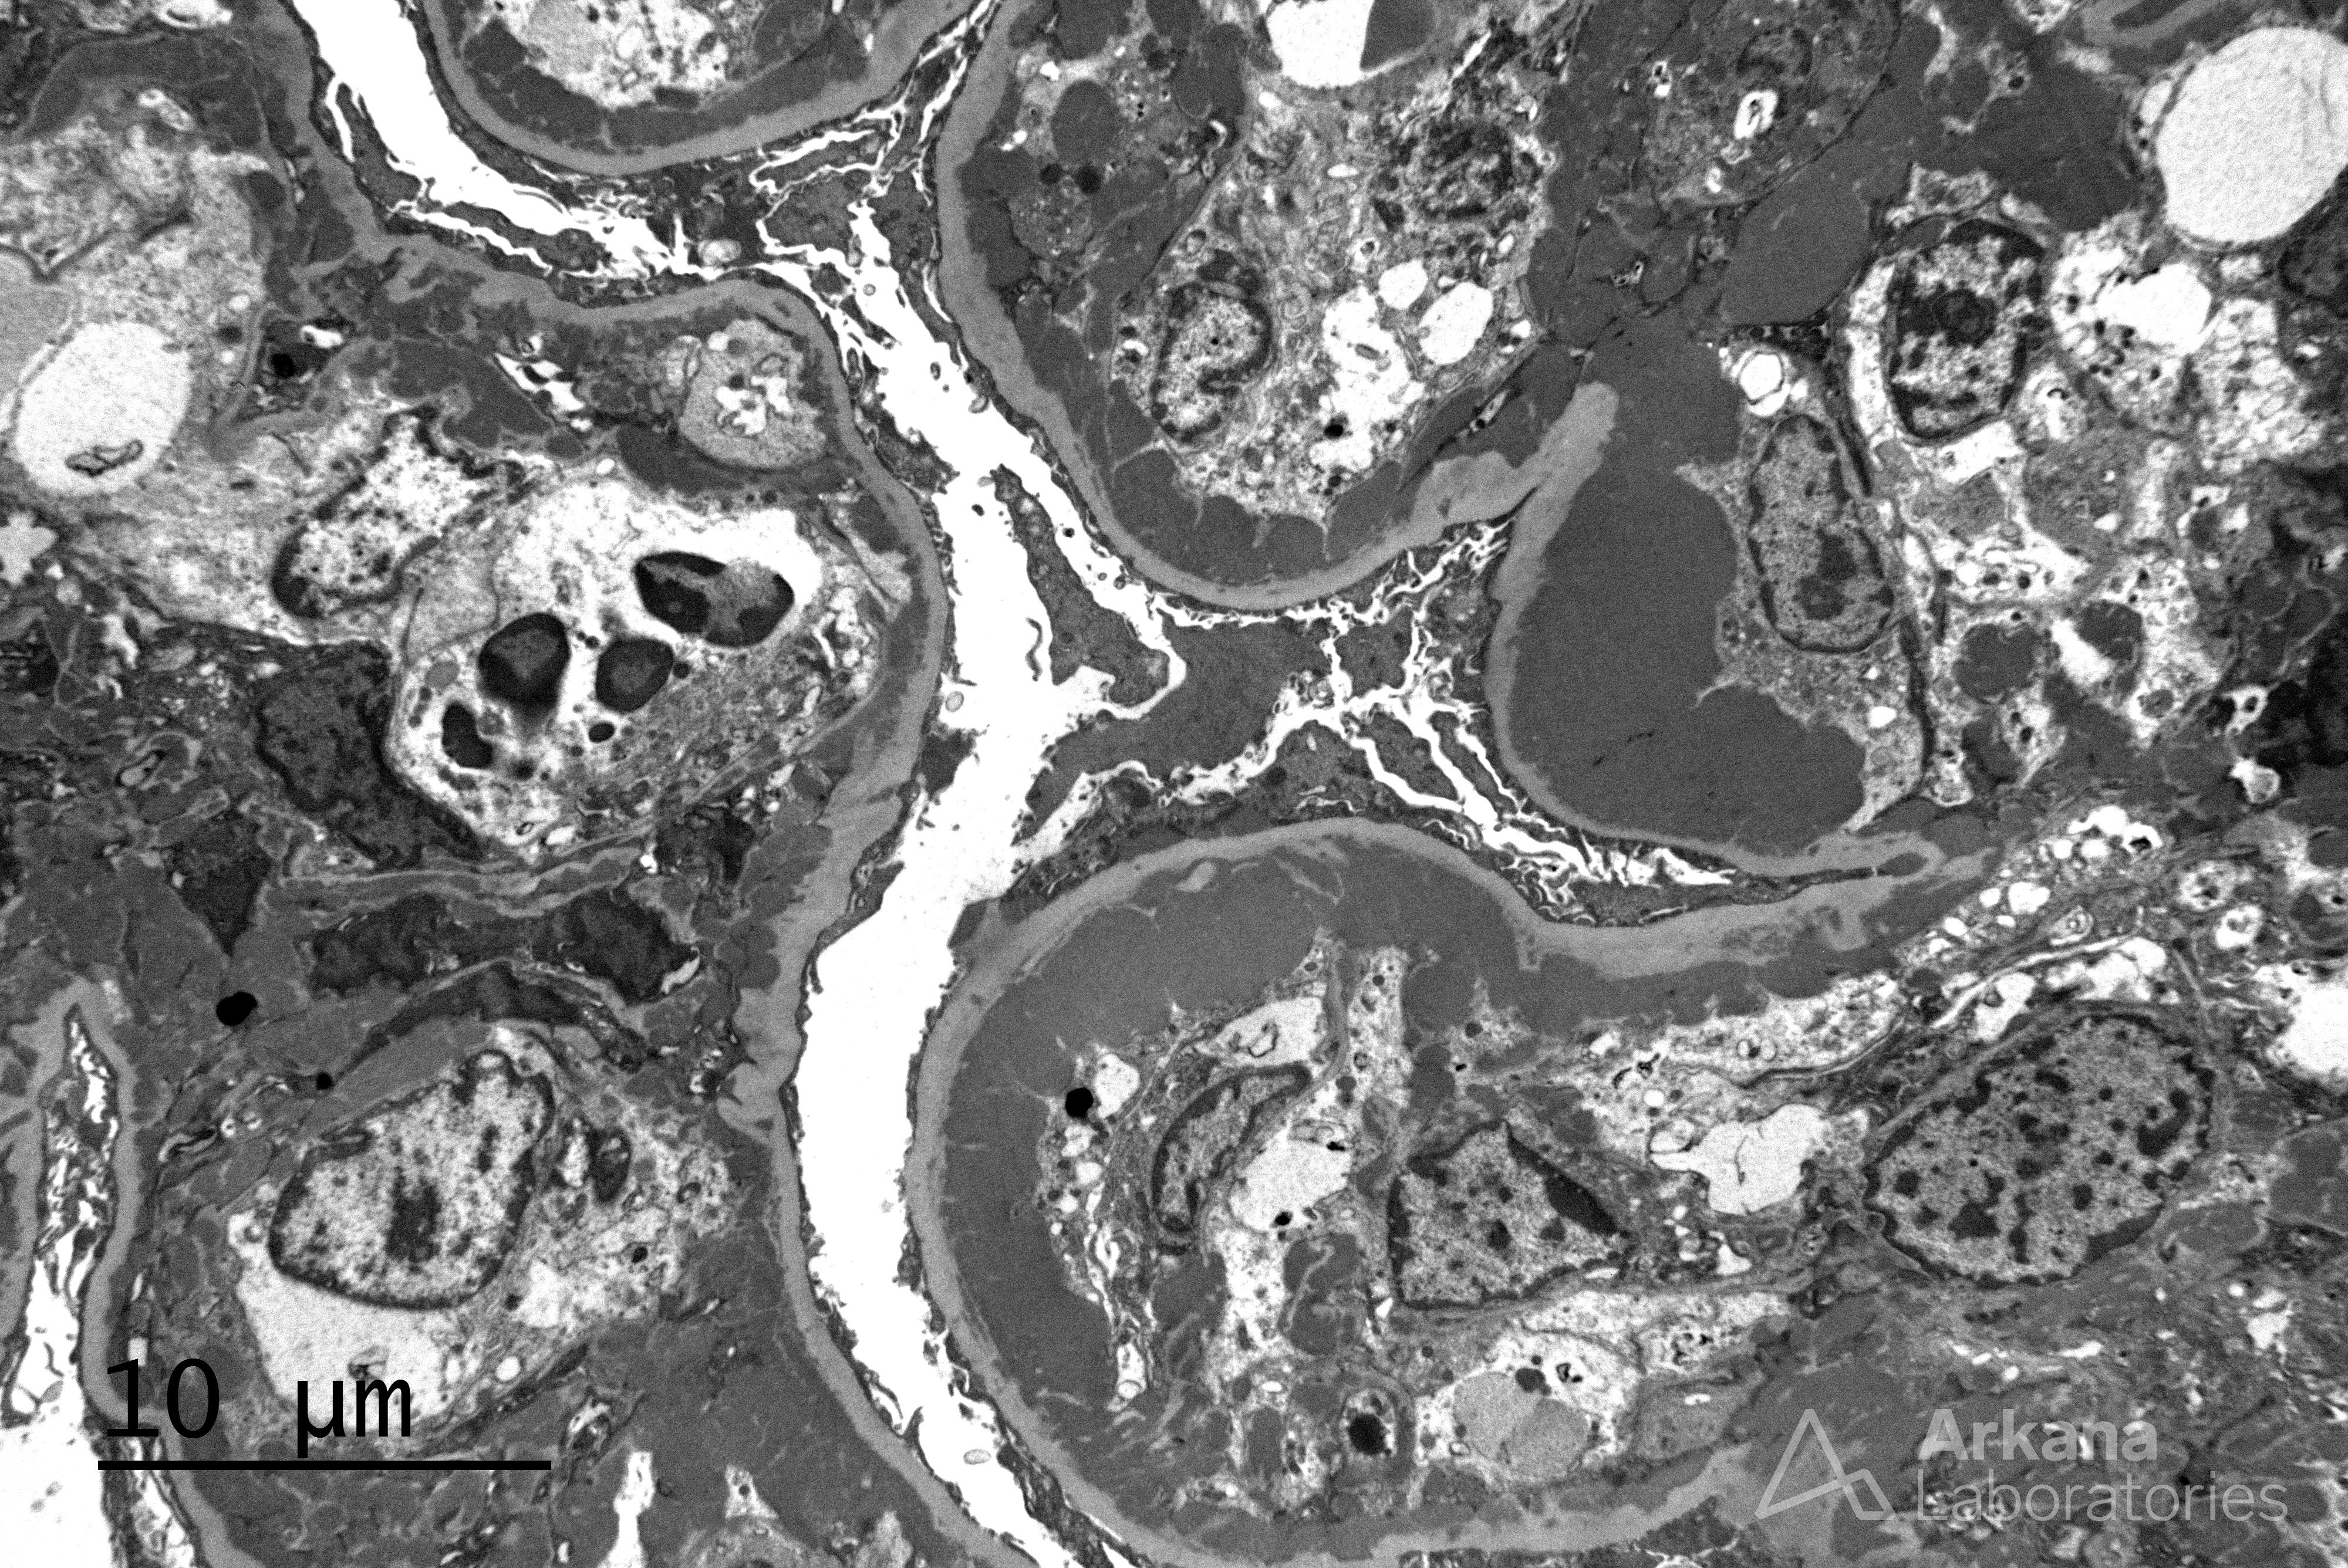

Wire Loops Formation in Lupus Nephritis on EM